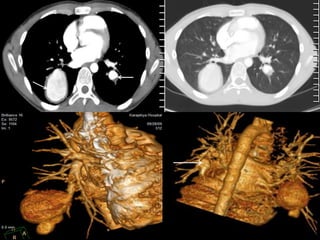

FINDINGS; 1). MASS IN LT LOWER LOBE.

2). LT HILAR & MEDIASTINAL ADENOPATHY.

3). TUMOUR INVASION OF LT ATRIUM.

4). TUMOUR INVASION OF LT PULMONARY ARTERY

ADVANCED BRONCHIAL CA